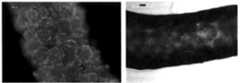

도 17. 비드의 생체적합성을 예증하는, 0.1M EDC 가교된 젤라틴 비드가 주사된 신장의 조직학 (1주).

도 18. 주사 후 1주 시점에, 가교된 젤라틴 비드의 분해를 보이는 신장 단편의 조직학적 평가.

17. Histology of kidney injected with 0.1 M EDC crosslinked gelatin beads (Week 1) demonstrating biocompatibility of beads.

18. Histological evaluation of kidney fragments showing degradation of crosslinked gelatin beads one week after injection.